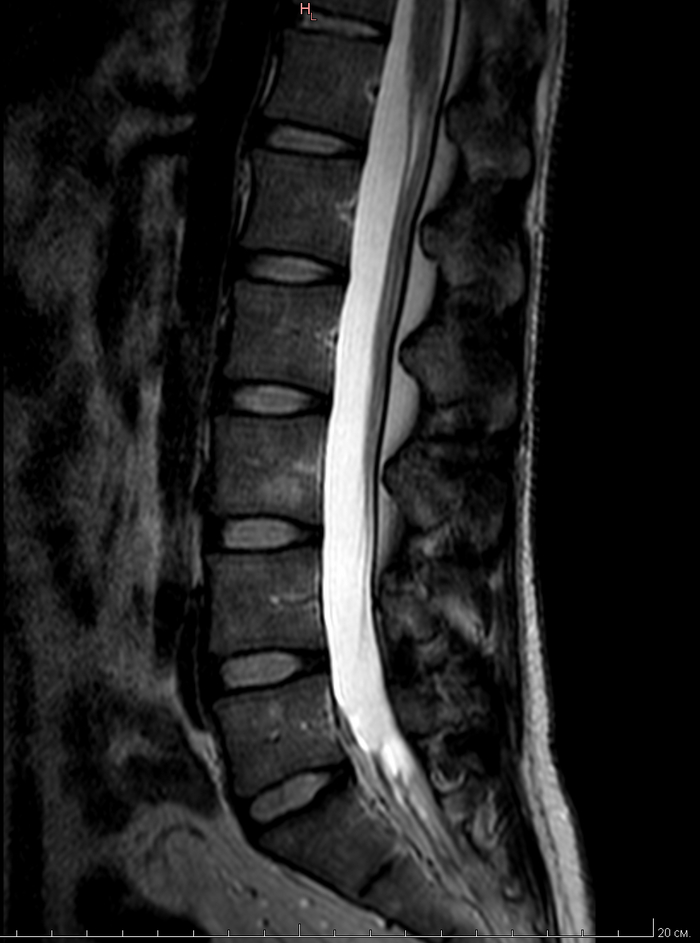

МРТ всех отделов позвонка

К этому посту Мое первое МРТ в 32 годика и этому Пикабу, нужна помощь по здоровью(Невролога(Но это не точно))

Пришло заключение от МРТ центра, я понимаю что надо идти еще на консультацию невролога и т.д. Но может кто из пикабушников сможет расшифровать по нашему, что и как.

Ну и что мне дальше делать.